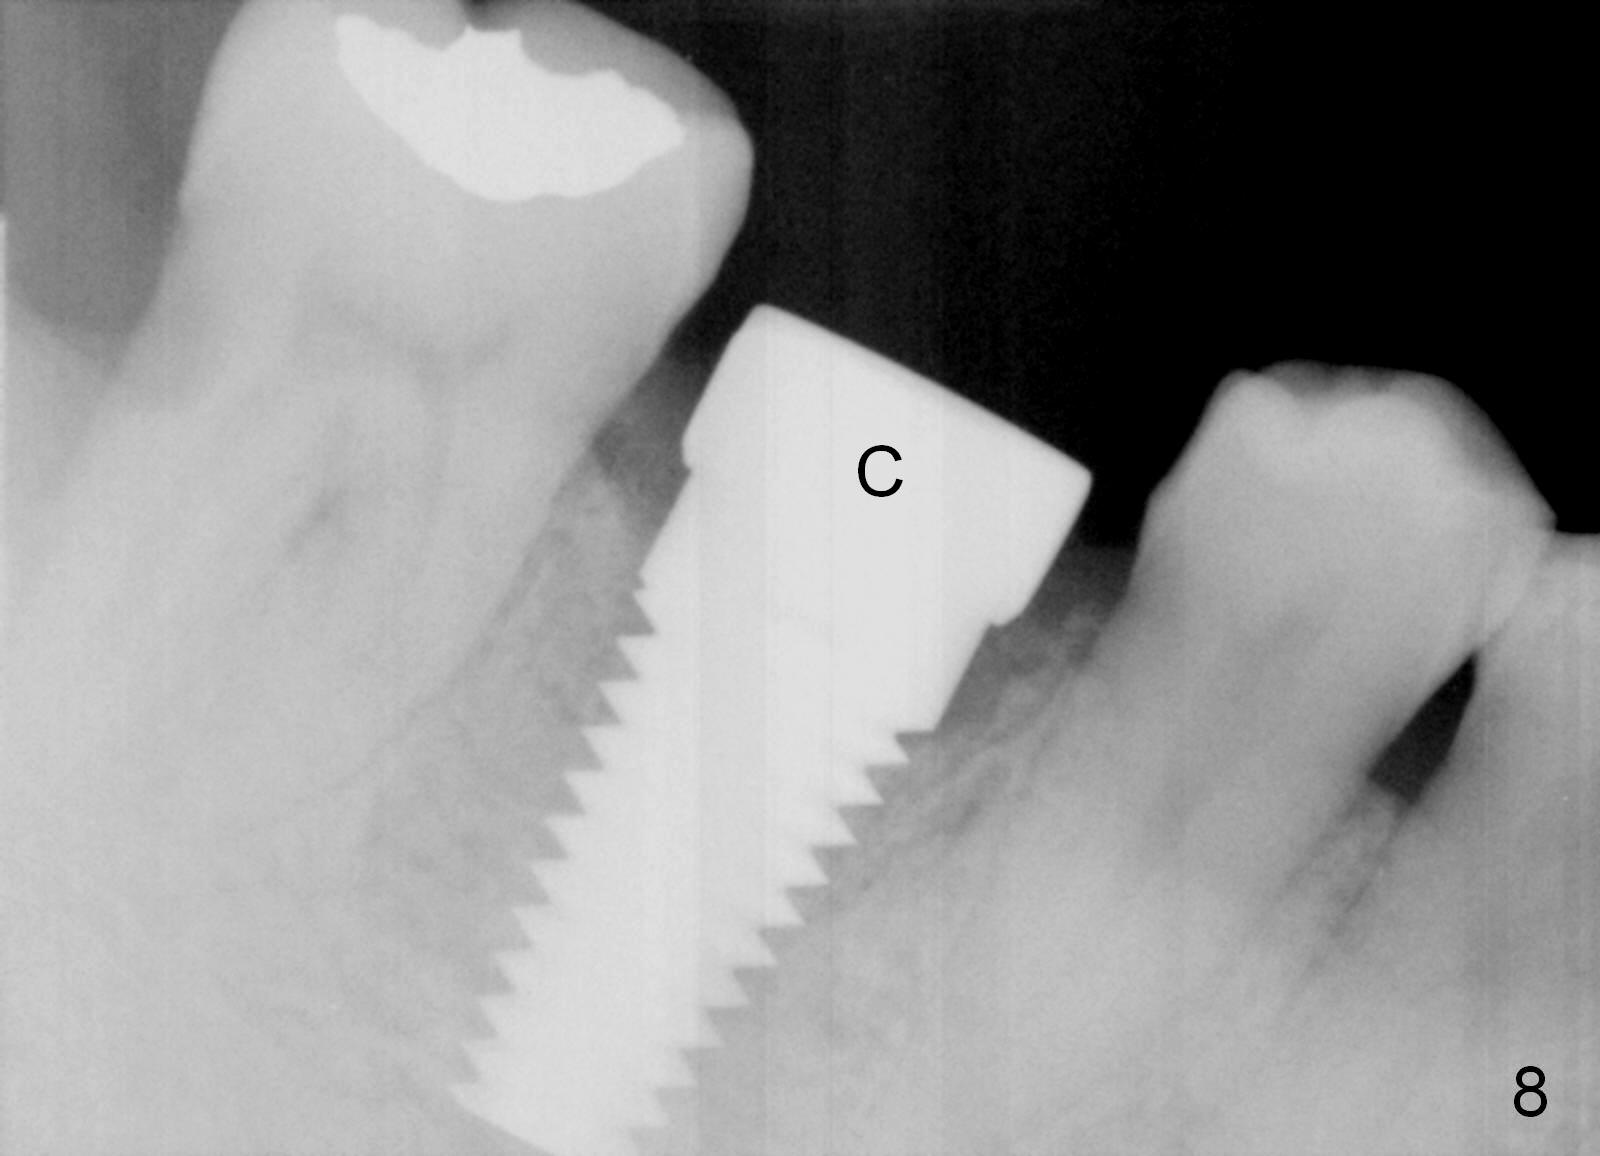

The next time the patient returns is 8.5 months postop (Fig.8,9). When an immediate provisional is not provided, the patient tends not to return early. In fact, retention of an immediate provisional and confidence in it by the patient promotes early finish of treatment (permanent crown).